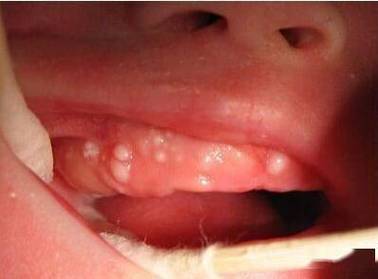

- 念珠菌感染 (鹅口疮): 这是一种由真菌(白色念珠菌)引起的感染,典型特征是口腔黏膜上出现白色、豆腐渣样或乳酪状的斑块,用力擦拭可以剥离,下方会有红色创面,这些真菌本身也会增加分泌物的粘稠感。